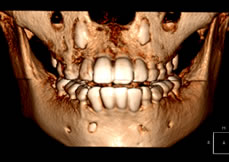

VR(ボリュームレタリング)では表面から内部のデータもあらわした三次元構成です。 ![]() ![]() |

歯科用CTでは、歯以外の骨の構造(柔らかい、硬い)、のう胞,腫瘍、神経管の位置などの立体構造がわかります。 |

被爆量は医科用のCTのなんと100分の1。 |